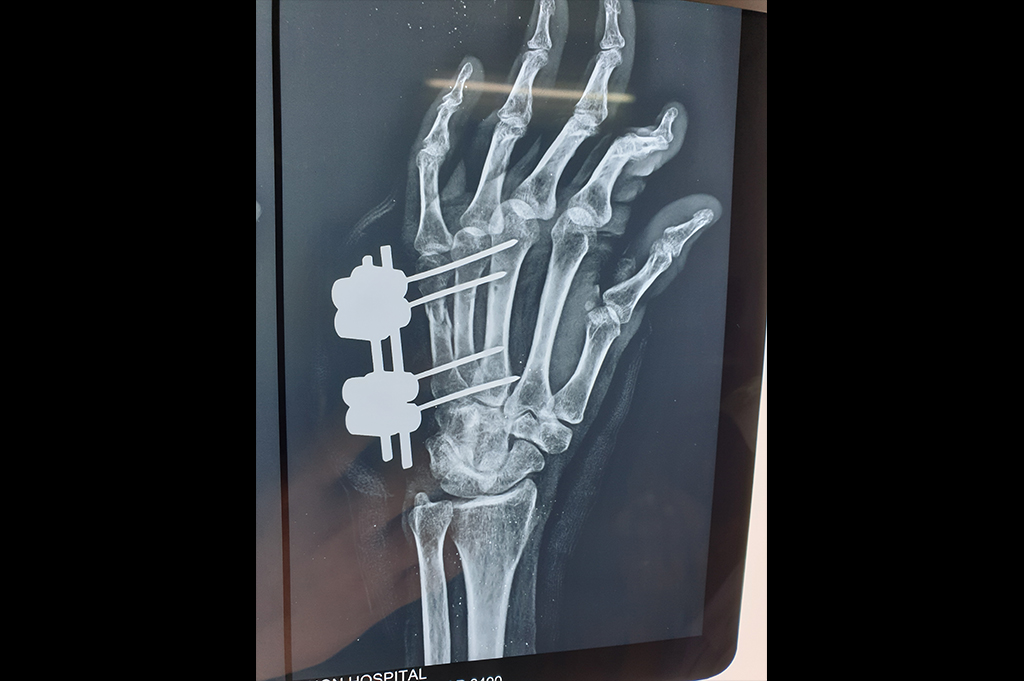

Finger Tip Injury - JESS

Metacarpal Fracture – External Fixator JESS